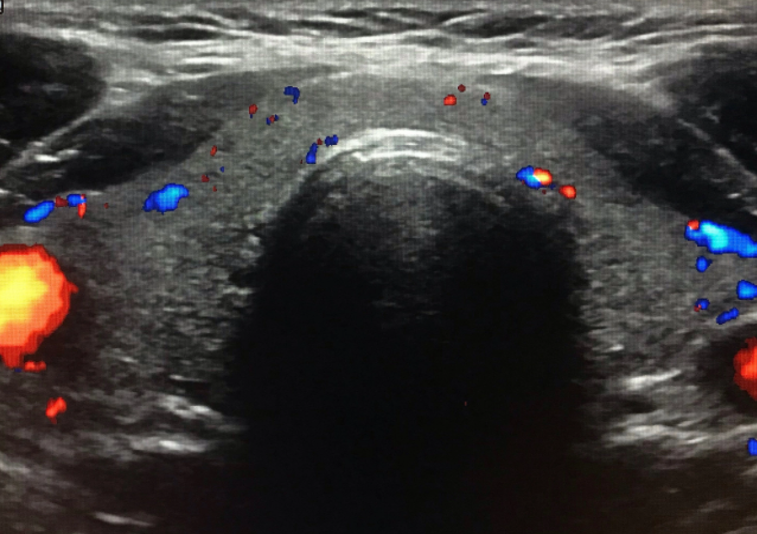

Breast Screening 20 minutes

Whole body ultrasounds provide a non-invasive, painless, imaging option, allowing for the assessment of various organs without exposure to radiation.

This screening can help identify abnormalities such as tumors, cysts, or vascular issues at an early stage, potentially improving treatment outcomes. Our general screening exams include: breast, thyroid, kidneys, liver, spleen, aorta, pancreas, and calf veins.